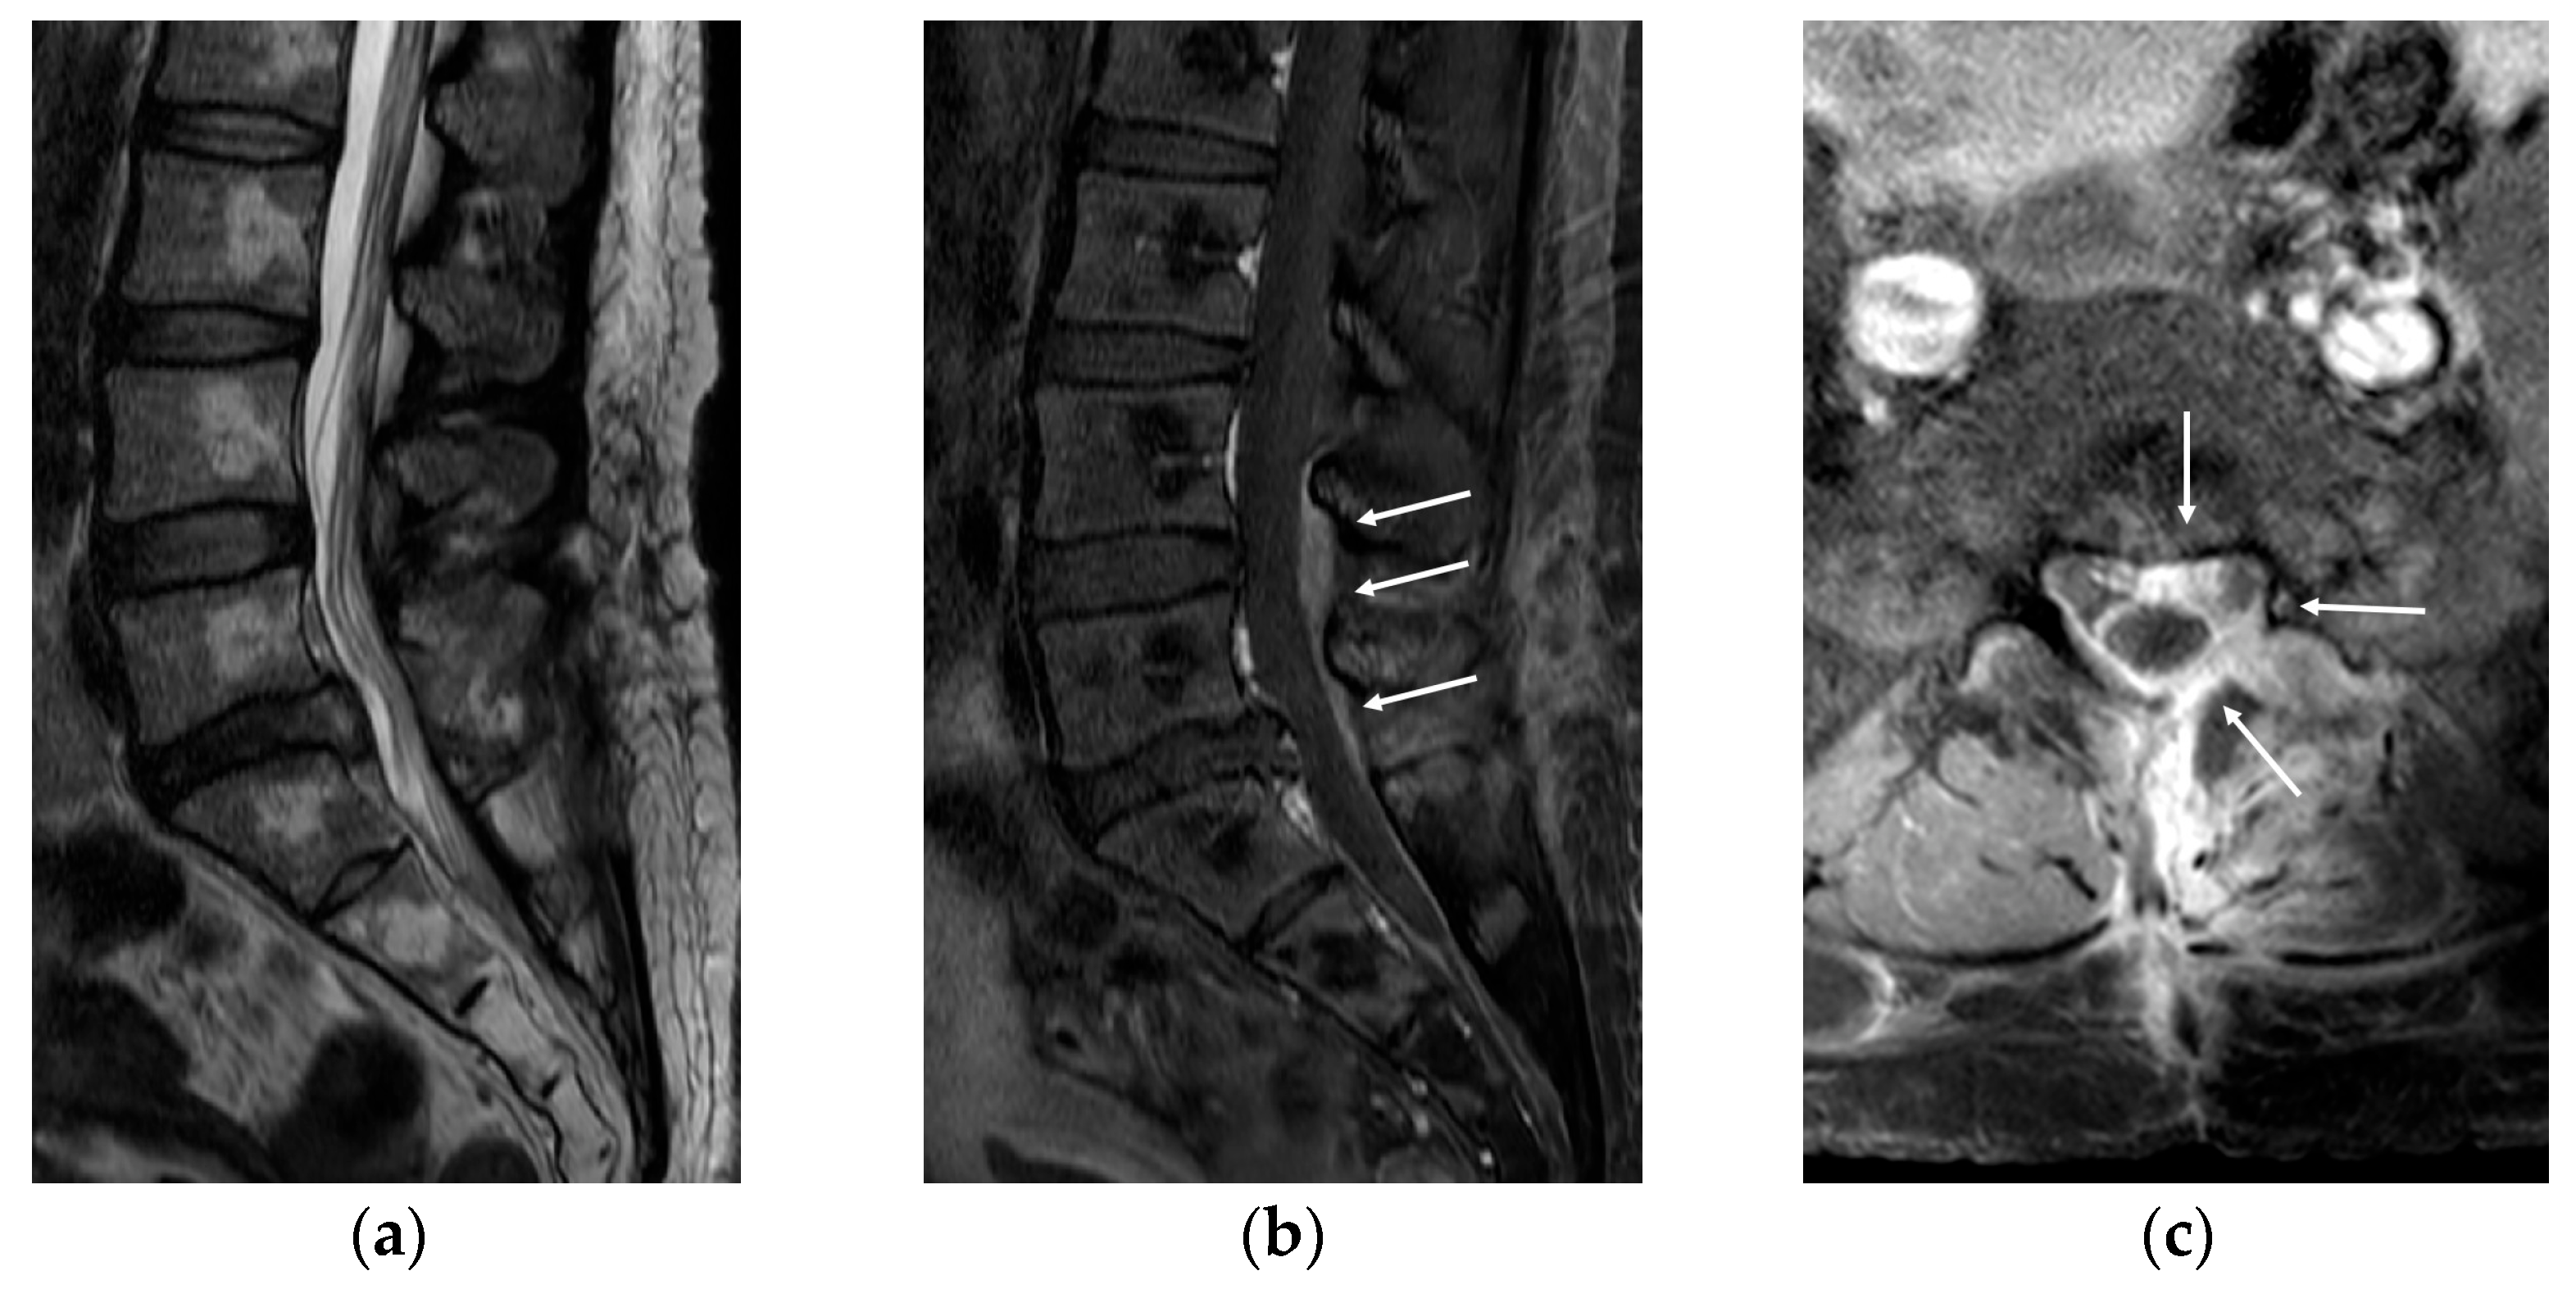

Eleven days after surgery, she was admitted to the emergency room due to severe pain in her back and left lower extremity. There was no clinical evidence of systemic infection (normal body temperature and no elevation of inflammatory marker) or wound problem (clear wound without local heating, redness, or discharge). MRI revealed no evidence of recurred or remnant disc. However, diffuse enhancement at the posterior epidural space from L4 to S1 levels and around the peridural space at the L5/S1 level (Figure 2) was noted. Conservative treatment, including root block, did not work; therefore, we decided to conduct revision surgery (L5/S1 posterior lumbar interbody fusion).

Figure 2.

Magnetic resonance imaging (MRI) was conducted to assess the recurrent pain in her back and left lower extremity at 11 days after surgery. (a) MRI revealed no evidence of recurred or remnant disc. (b,c) However, diffuse enhancement was noted at the posterior epidural space from L4 to S1 levels (arrows) and around the peridural space at the L5/S1 level (arrows).